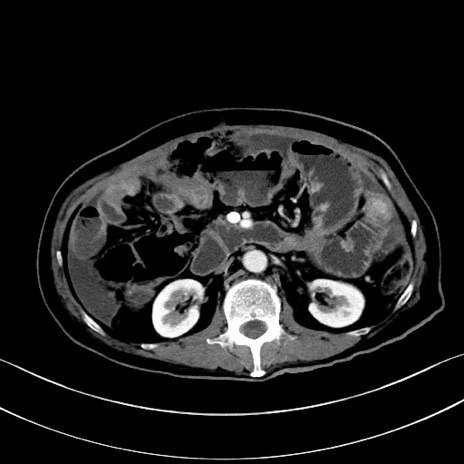

症例28(横断像)

【症例】60歳代男性

【主訴】嘔吐

【現病歴】胃癌にて胃全摘後。食思不振が悪化し、夜中に嘔吐することがある。

【既往歴】胃癌、胃全摘、脾摘、胆摘後

【データ】WBC 5900、CRP 10.56